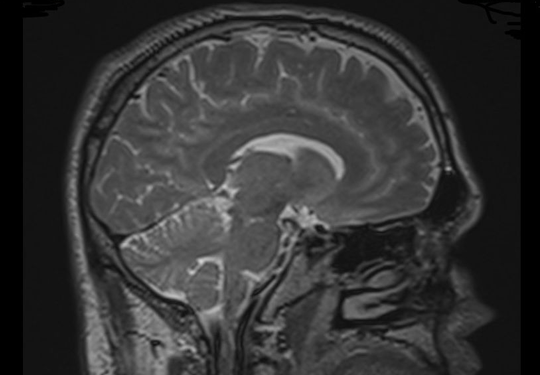

"Normal MRI – DTI”

A concussion or blast injury causes a diffuse injury throughout the brain: multiple small lesions that are not detectable at a gross anatomical level. The neuropathology of the injury must be evaluated in a different way. The genius of brain MRI with DTI application is that physiological changes in the brain which represent injury are demonstrated in conjunction with tractography (the drawing of fiber tracts in the brain). Interruptions in the fiber tracts are consistent with injury at that location. Damaged fiber tracts interfere with network functions of the brain.